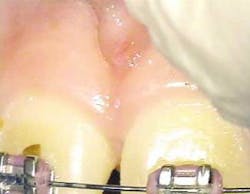

After infiltration of 1cc of local anesthetic solution, the Er:YAG laser (OpusDuo, OpusDent USA) was used at 350mj with a 1,000-micron, contact sapphire tip and heavy water spray to gently ablate the frenal attachment and underlying muscle tissue down to the level of the periosteum (figures 2, 3, and 4). Once this is accomplished, there is a small defect in the vestibular mucosa and interdental papilla where the frenal attachment and muscle once was. There is no charring, no burned tissue, and free bleeding in the site (figure 5).

Once the Erbium part of the procedure is completed, the Superpulsed CO2 (OpusDuo, Opusdent USA) is then used to simply coagulate and gently cauterize the bleeding site. With this approach, the practitioner can immediately pick up a focused 90-degree handpiece and apply 1.5 watts in the Superpulsed noncontact mode. This is accomplished with a circular sweeping pattern to gently coagulate the superficial bleeding layer to a depth of 75-100 microns (figures 6 and 7).

With the dual approach to this procedure, healing at 16 days is profound and complete (figures 8 and 9). Any excess thermal deposition or damage to the tissue is avoided when both lasers are used, and the problematic frenum attachment inhibiting further orthodontic correction is completely removed.